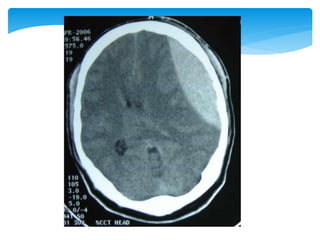

 Primarily frontaland temporal lobes, but other sites are possible  Impact at the time of injury  Most patients with subdural haematoma have associated contusions of the brain  Greatly dependent on size and location Cerebral Contusions

Approach To CT ScanCT scan

Approach To CTScanCT scan Bone window Look for fractures- •Cranial vault •Skull base •Facial bones Tissue window •EDH •SDH •ICH •Contusions •Pneumocephalus •Hydrocephalus •Cerebral edema Subdural window •Any hemorrhage •Soft tissue and bone •Fontanel •Suture lines •Foreign bodies